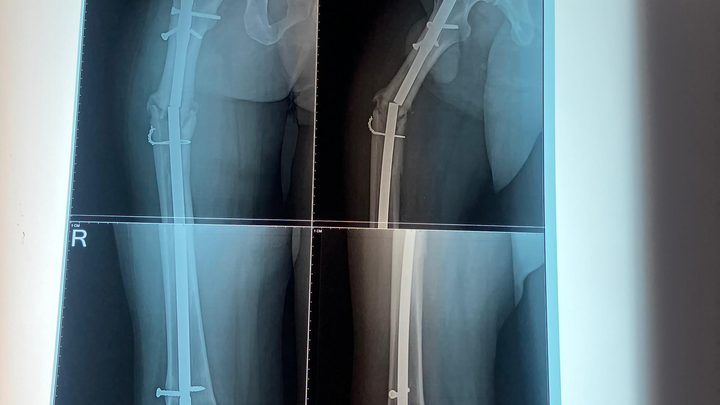

Today, my brother is in unbearable pain. Recent X-rays show that his femur appears broken again. His leg is deteriorating, and without urgent surgery, he may permanently lose it.